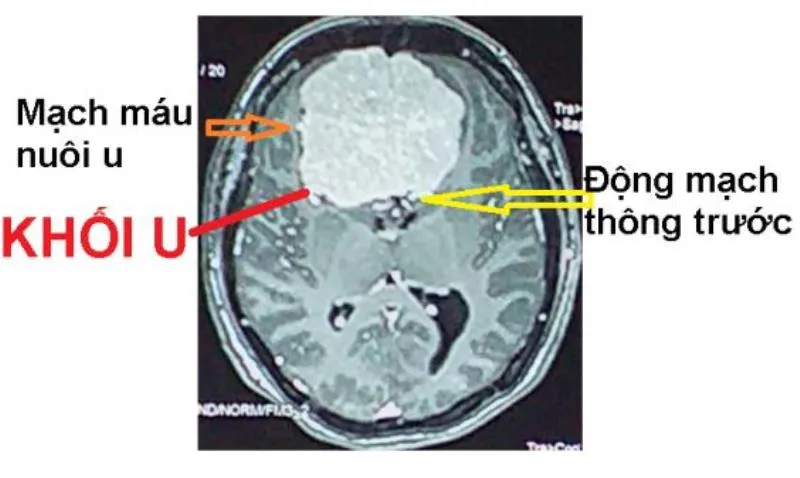

Ngay lập tức, các bác sĩ tiến hành khám lâm sàng, bệnh nhân có triệu chứng thần kinh trung ương, phù gai thị và kết hợp thực hiện cận lâm sàng kiểm tra. Kết quả chụp cộng hưởng từ có tiêm chất tương phản, ghi nhận khối choáng chỗ ngoài vùng trán kích thước # 6 x 6.5 x 5cm, ép não thất hai bên, kết luận u màng não khổng lồ.

Các bác sĩ tiến hành hội chẩn quyết định chụp và nút mạch tiền phẫu số xóa nền, nhằm mục tiêu tắc mạch máu nuôi khối u, sau đó thực hiện phẫu thuật bóc tách khối u màng não.